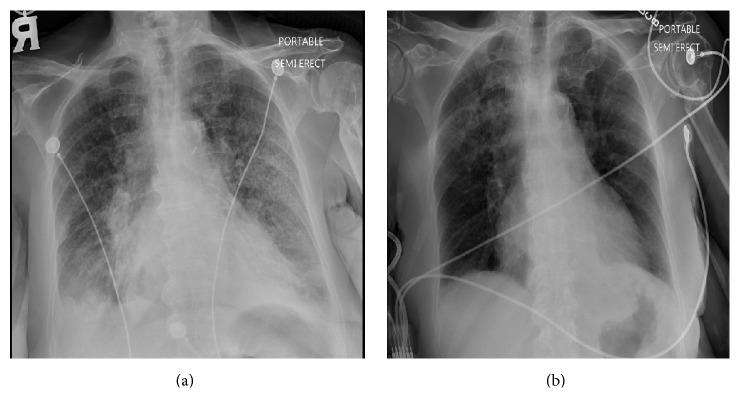

支气管内超声引导下经支气管针吸活检术(EBUS-TBNA)越来越多地用于胸部恶性肿瘤的诊断和分期。坏死性淋巴结的发现会引发对感染性病变和恶性肿瘤的担忧。淋巴结内超声/EBUS显示的无血流低回声区提示感染或恶性肿瘤等病变。对吸出液的检查有助于诊断;清亮的吸出液通常提示支气管源性或纵隔囊肿,脓性物质提示脓肿或坏死性淋巴结。生长中的肿瘤细胞需要血液供应;如果由于快速生长的恶性肿瘤导致血管基质不足,可能会导致大片中央缺血性坏死。淋巴结的坏死性吸出物并不总是由感染引起。EBUS-TBNA中吸出液体的情况罕见,当获得脓性液体物质时应考虑恶性肿瘤。我们报告一位老年女性,她接受了支气管镜检查及EBUS-TBNA,以评估上肺结节和纵隔淋巴结肿大。针吸活检获得了脓性物质,支气管内活检和纵隔芯针活检显示为鳞状细胞癌。